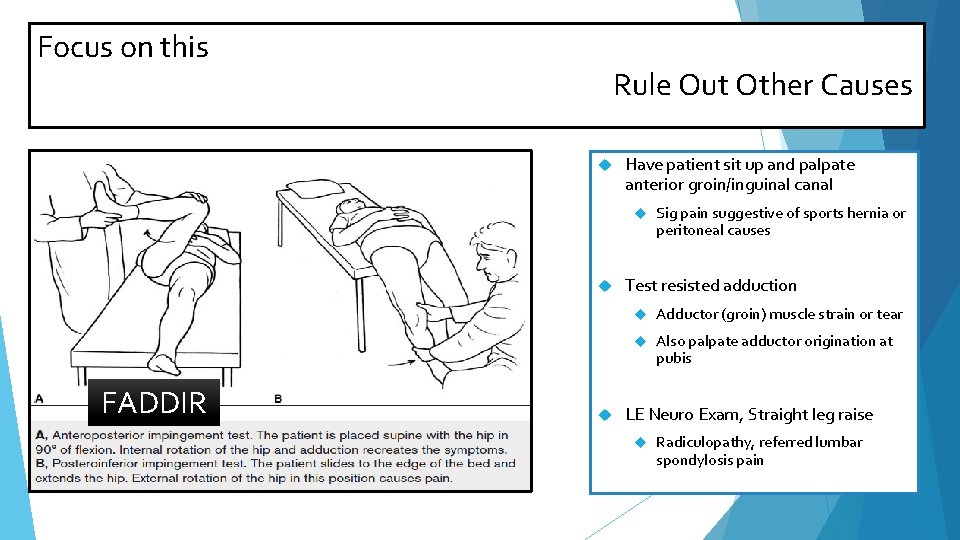

Focus on this Rule Out Other Causes Have patient sit up and palpate anterior groin/inguinal canal FADDIR Sig pain suggestive of sports hernia or peritoneal causes Test resisted adduction Adductor (groin) muscle strain or tear Also palpate adductor origination at pubis LE Neuro Exam, Straight leg raise Radiculopathy, referred lumbar spondylosis pain